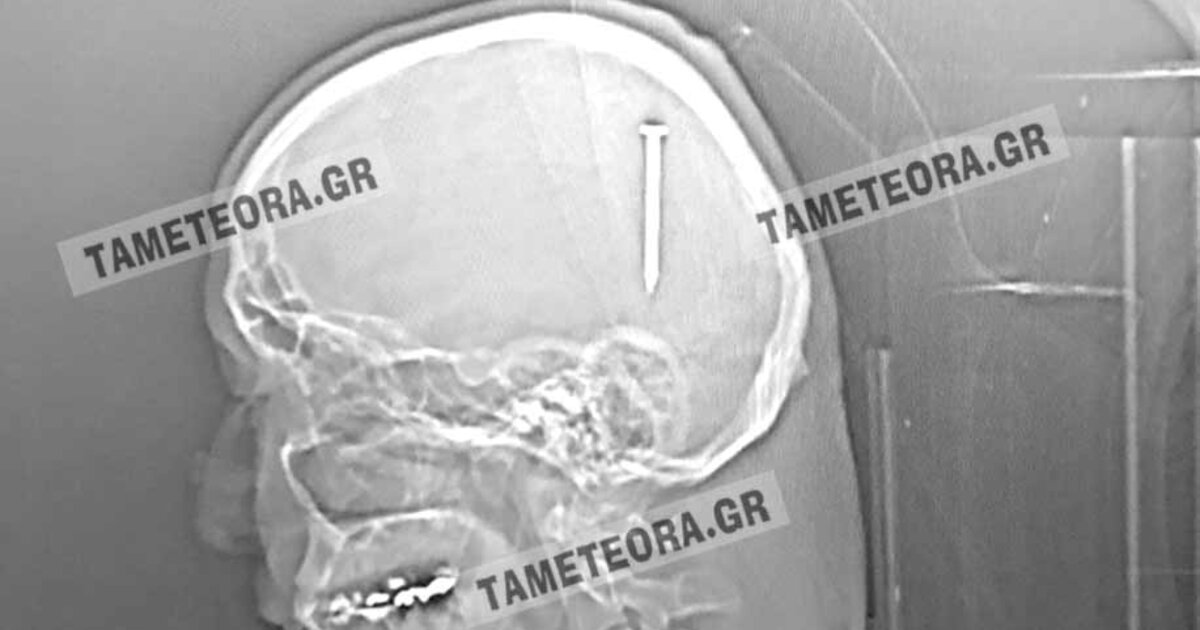

Καρφί 5 εκατοστών σφηνώθηκε στο κεφάλι άνδρα

Όπως κατέγραψε η ιστοσελίδα tameteora.gr ο άνθρωπος βρέθηκε ξαφνικά με ένα καρφί 5 εκ. στο κεφάλι του κατά το διάστημα εργασιών που έκανε.

Πρόκειται πραγματικά για ένα σπανιότατο περιστατικό, ένα πραγματικό θαύμα, όπως λένε οι κάτοικοι στην περιοχή, καθώς αν το καρφί βρισκόταν ελάχιστα χιλιοστά από το σημείο που σφηνώθηκε, θα ήταν πολύ επικίνδυνο για την υγεία του συμπολίτη μας με άγνωστα αποτελέσματα.